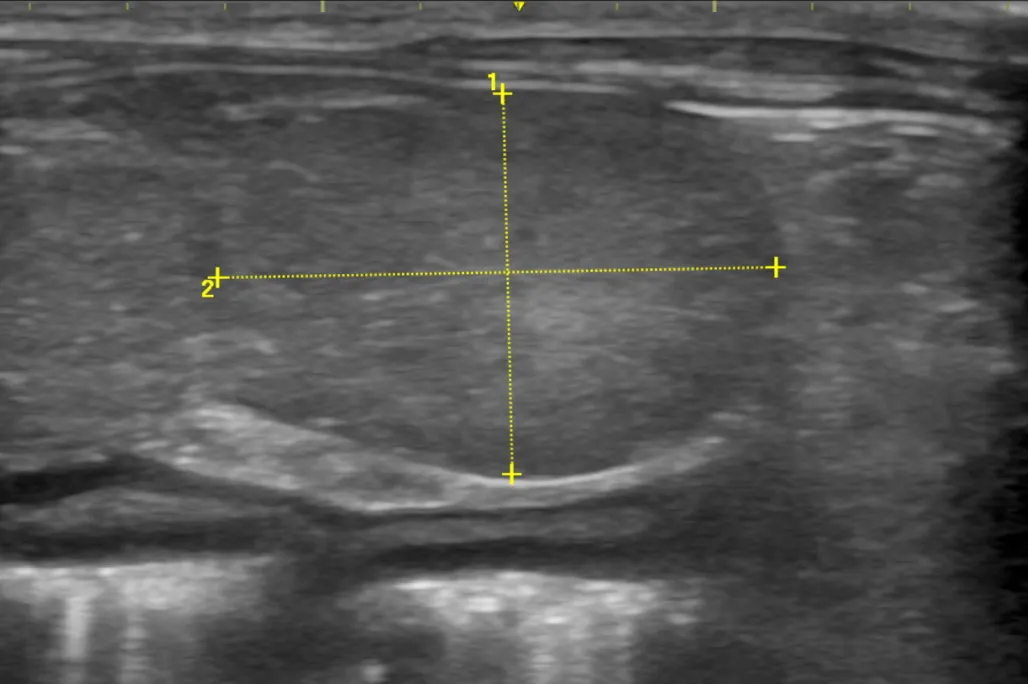

腹部超音波検査では左肝区域に13×20mm大の腫瘤が1つ、中央肝区域に1cm未満の結節が1つみられました。左肝区域腫瘤の内部構造はやや不整で、混合エコー性〜高エコー性、境界不明瞭、内部血流に著変なく、良性悪性どちらもありうる所見でした。ご家族は麻酔を必要とする精査(造影CT検査など)や外科手術(肝臓腫瘤切除)は希望されておらず、時間経過での腫瘤の変化で推定診断することにしました。

初診から2ヶ月経過したところで肝臓腫瘤に対して腹部超音波検査を実施したところ、左肝区域腫瘤は増大(16×33mm)しており、内部構造はより不整で、境界明瞭に変化していました。中央肝区域の結節に変化はありませんでした。時間経過による画像所見の変化を踏まえ、左肝区域腫瘤は肝臓の悪性腫瘍(肝細胞癌)の可能性が高いと暫定診断いたしました。ご家族には改めて2次診療施設でのCT 検査や外科手術についてご提案しましたが、余生は無理なく過ごすことを選択されました。本疾患だった場合に将来的にどうなるのかご説明をし、無治療で余生を過ごしていただくことになりました。